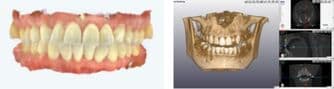

2診査(検査)・診断

お口やお顔のお写真、歯型取り、レントゲン写真を採得し患者様の状態をより精密に確認いたします。(診断料:55,000円)

検査内容

写真各種

X線写真各種

ISOデータ 精密検査の結果から患者様にあった治療方針・計画など最終的な治療のゴールについてご説明いたします。

検査した内容を分析し患者様の今の状況(現在の上下顎骨のバランスやその骨に対しての歯の位置や上下の歯の位置や角度が標準値と比較した状況のチェック)からどこまで治療が可能かのシュミレーションを作成します。また、具体的な期間、装置、費用の説明などを行います。

検査データの解析

解析したデータから治療ゴールの制作 -